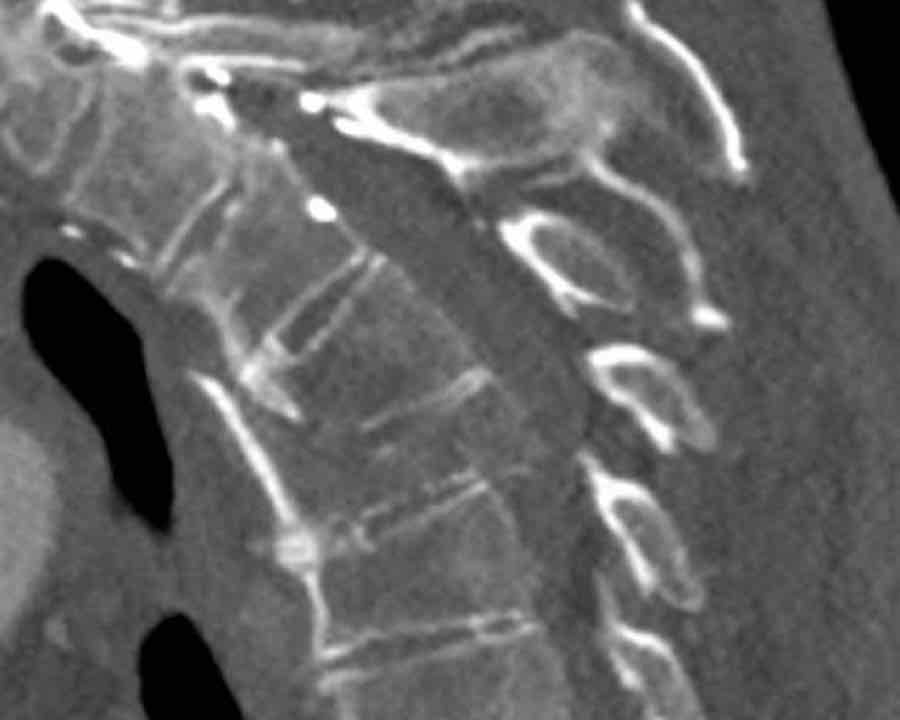

First look at the images.

What are the findings?

What is the highest AO-type of injury?

Findings

- Both facet joints are perched or displaced (black arrows).

The displacement of the vertebrae (white arrow) is not as striking as in previous cases. - There are fractures of the spinous processes on multiple levels.

This is a common feature in C injuries. - Pay attention to the chip fractures on the endplates.

Conclusion

Type C + A1 injury.